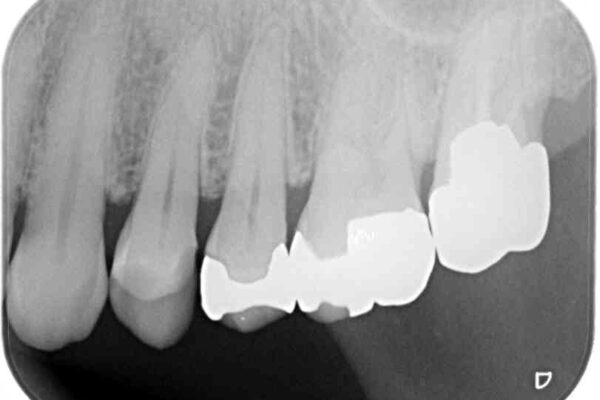

奥歯の銀歯が外れてしまったため、セラミック治療を希望された患者様です。

セラミックインレーによる修復治療を実施しました。

正面から見える場所であったため、セラミックインレーで自然な口元にすることができました。

治療前

• 外れてしまった銀歯 セラミックインレーで自然な仕上がりに 治療前画像